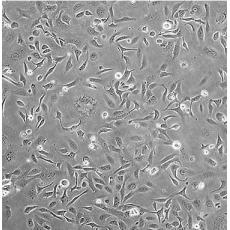

SK-OV-3 [SKOV3]

產(chǎn)品名稱 SK-OV-3 [SKOV3]

中文名稱 人卵巢癌細(xì)胞

組織來源 卵巢漿液性囊腺癌;腹水轉(zhuǎn)移;女性

生長特性 adherent

形態(tài)特征 epithelial